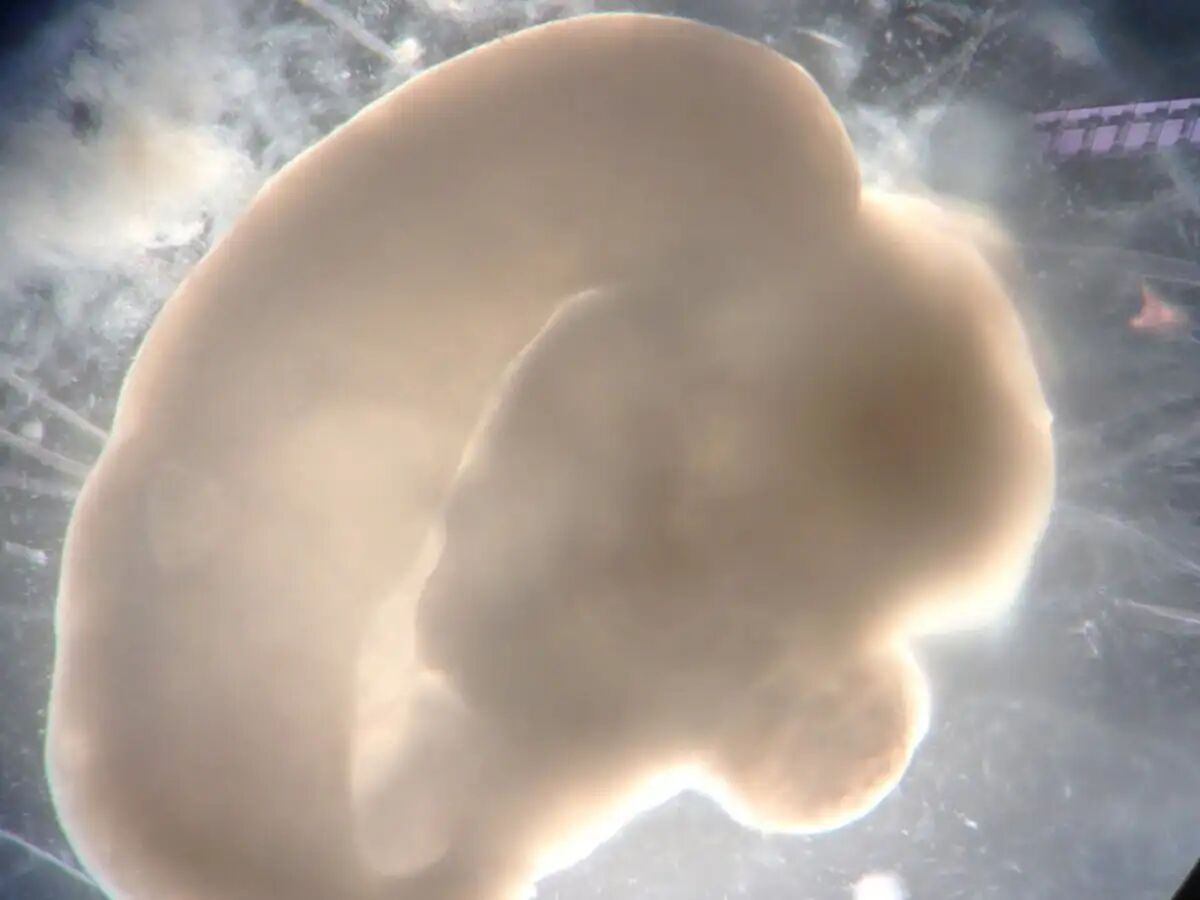

彩图展示了充满神经连接的类脑器官